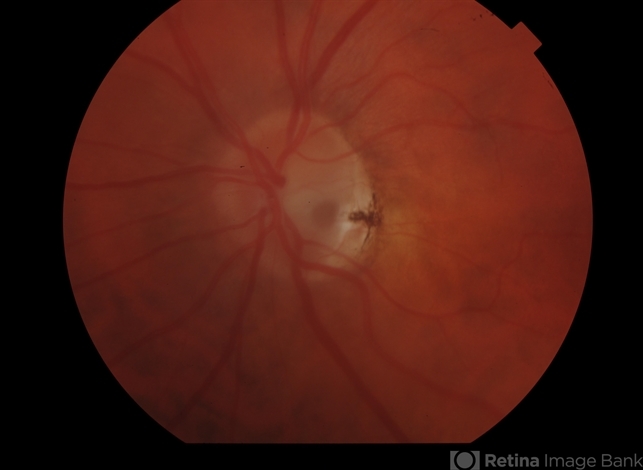

- congenital optic nerve pit, Optic nerve pit

- 65 year old female with optic nerve pit. Asymptomatic, continued observation.